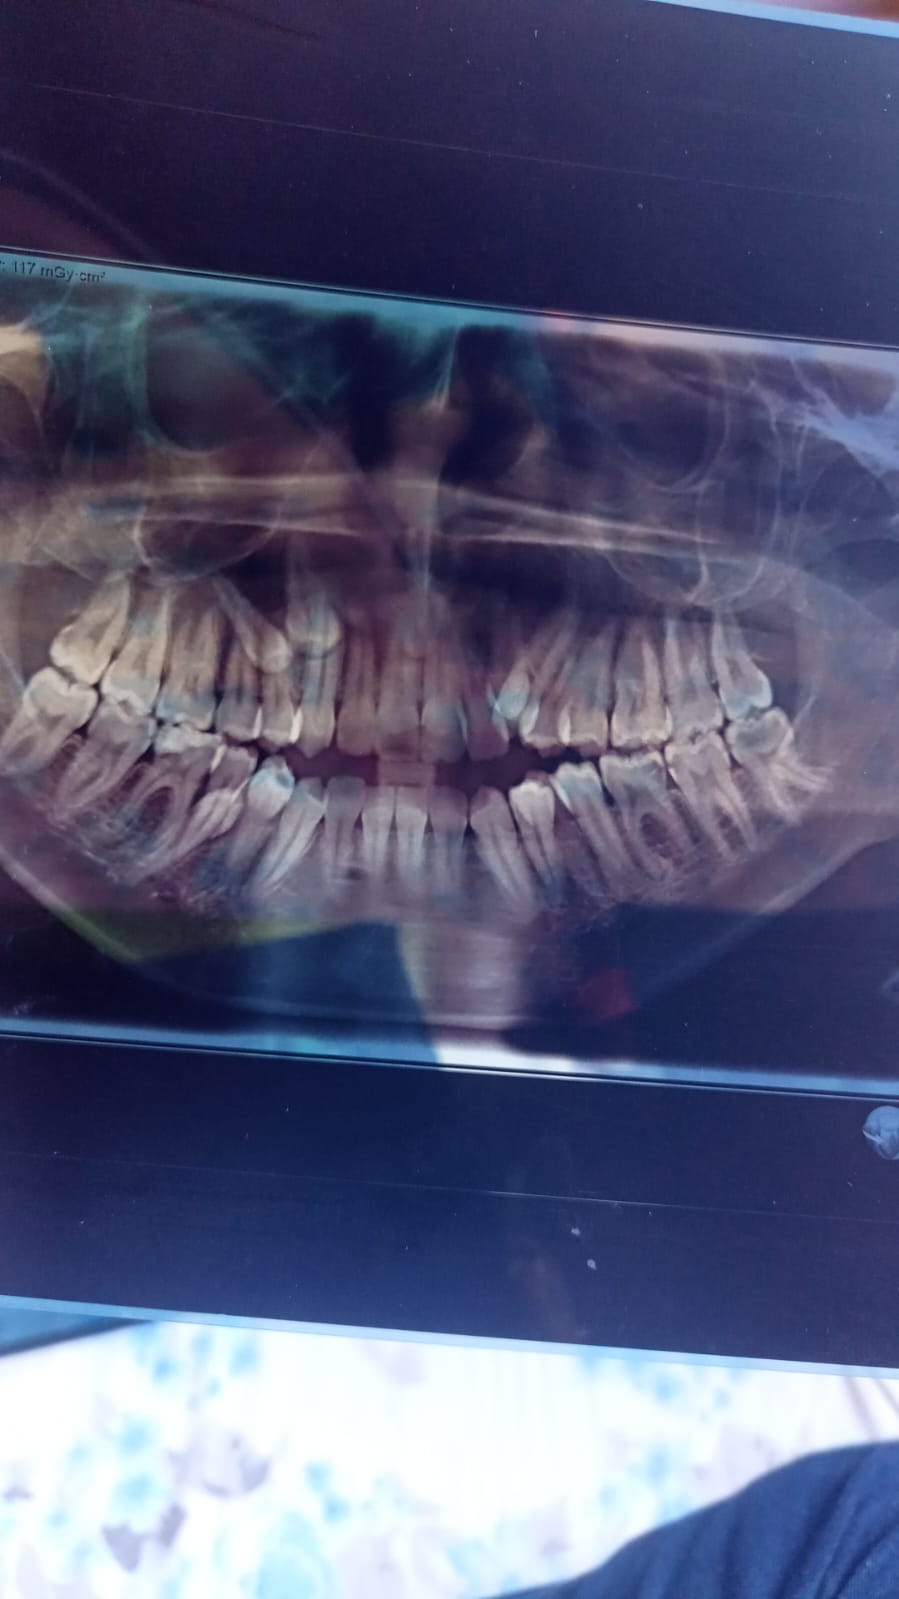

ما تشخيص هذه الأشعة؟

اريد تشخيص الاشعه